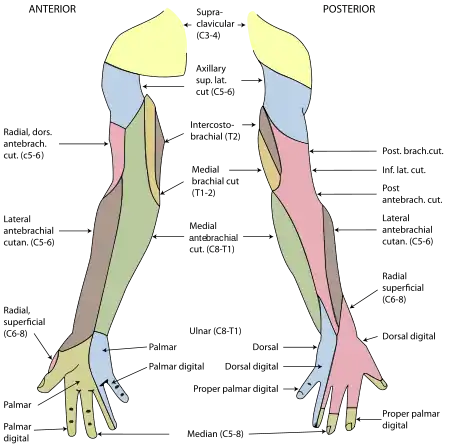

Nerve supply and passage

The skin around the shoulder is supplied by C2-C4 (upper), and C7 and T2 (lower area). The brachial plexus emerges as nerve roots from the cervical vertebrae C5-T1. Branches of the plexus, in particular from C5-C6, supply the majority of the muscles of the shoulder.[3]